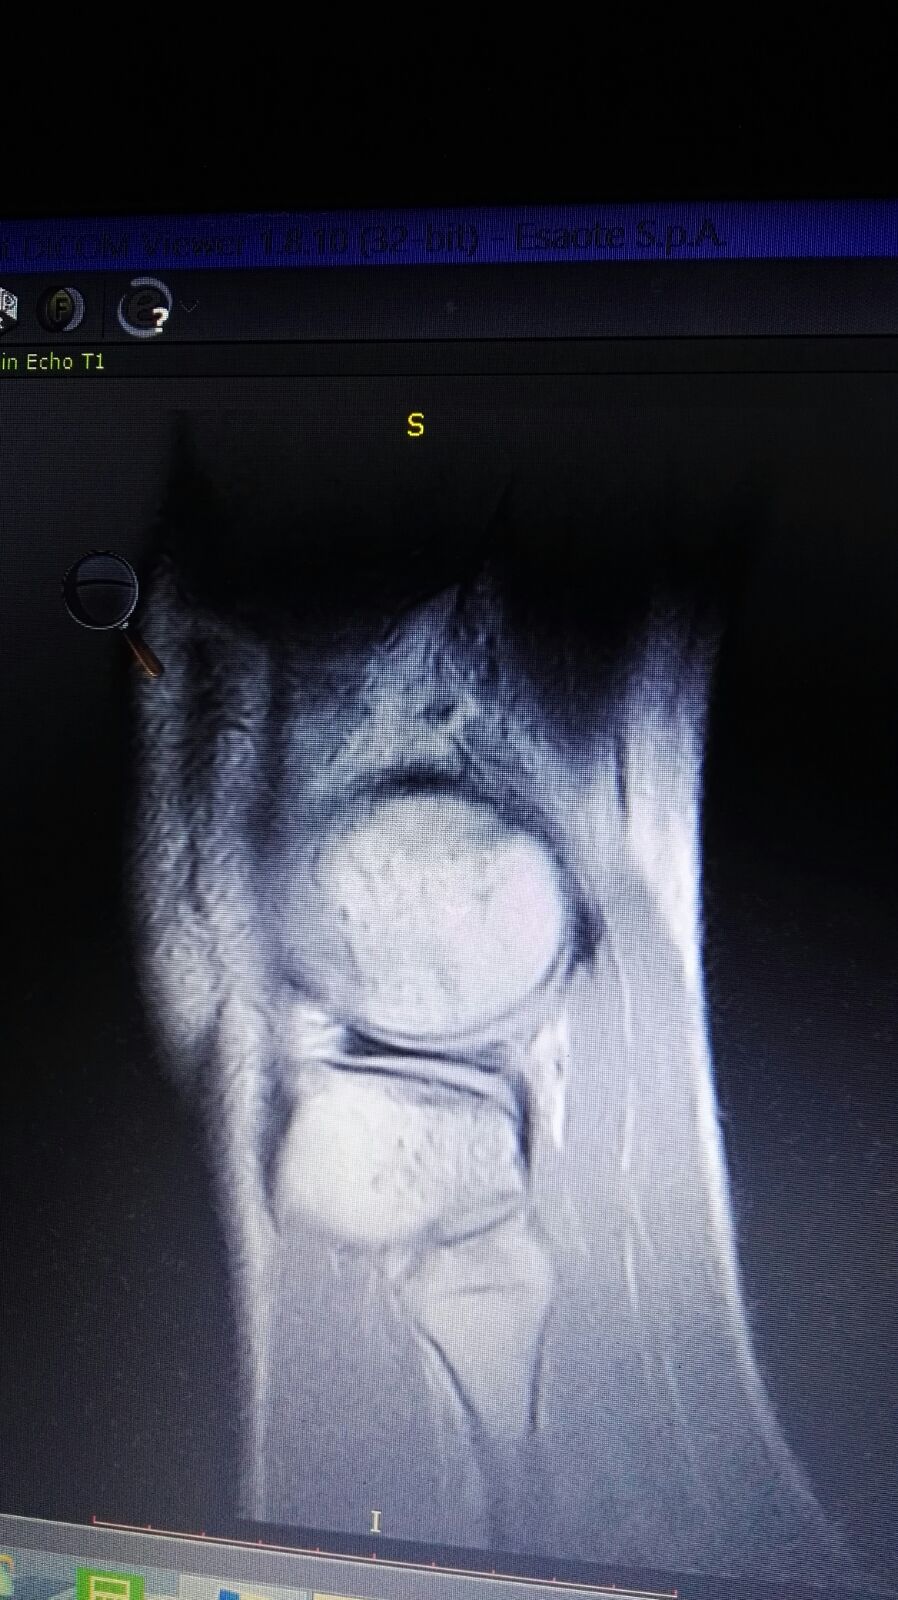

Salve mio marito circa un mese fa giocando a calcio si è fatto male il ginocchio. Essendo fuori per lavoro e riuscito solo a farsi una RSM LE mandi le foto se gentilmente può vederle. Lui è in addestramento per una missione volevo sapere se in un mese può farcela a guarire grazie mille.

IMG-20180301-WA0033.jpg

[ 205.56 KiB | Osservato 1320 volte ]